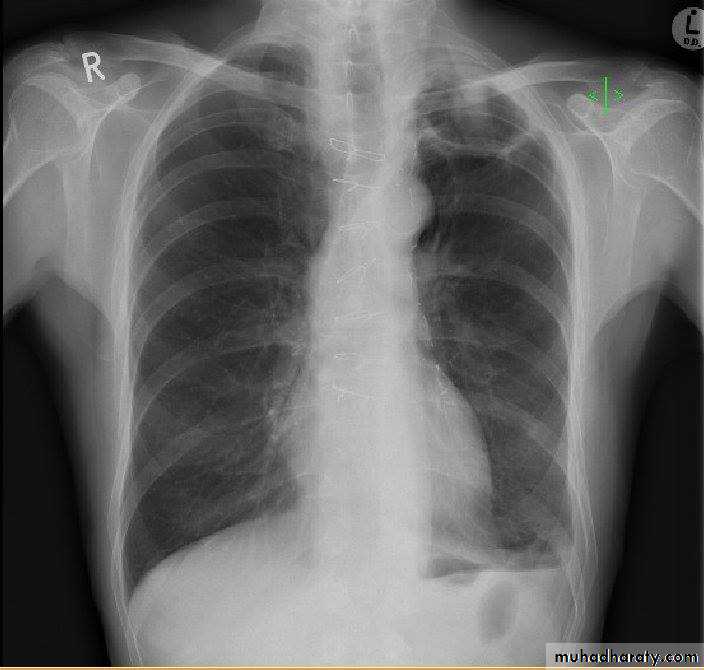

Focal lung diseases-nodule

- mass

-cavity

Pulmonary nodule /s1) Bronchogenic CA ( spiculated )

2)Metastasis ( multiple & different size & distribution )

3) Tuberculoma

4) hamartoma

Both are : solitary , peripheral & contain calcification )

5)Hydatid cysts

6)AVM (arterio-venous malformations which show feeding vessels